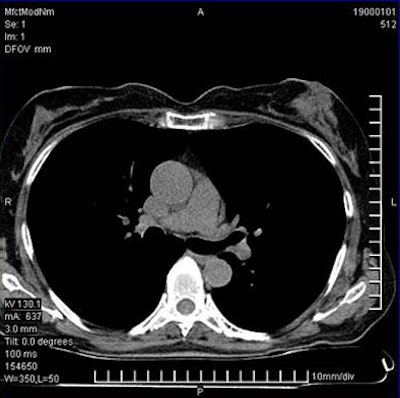

![]() |

| Coronary artery calcium scans were performed on a 64-detector-row scanner using 3-mm contiguous scans from the carina to the apex of the heart, with ECG triggering of 60% to 70% of the RR interval. |